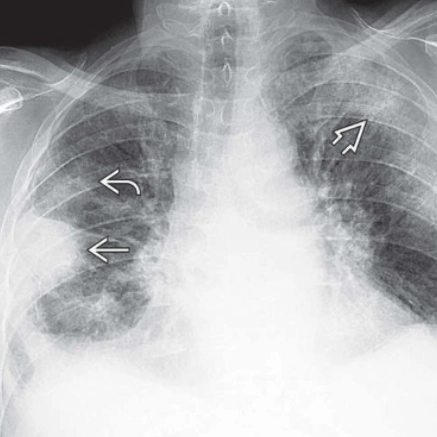

Viêm phổi tăng bạch cầu ái toan mạn tính (Chronic Eosinophilic Pneumonia - CEP)